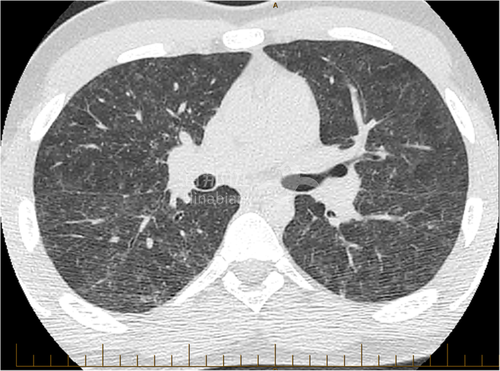

并且CT显示双侧对称弥漫性斑片状磨玻璃影(肺部明显受损)并伴有小体积腺病,然而未见微结节。

然而,没过多久,这名17岁患者的父母、弟弟还有祖母都陆续出现了咳嗽和不同程度的呼吸困难,CT检测也出现了类似的症状,对该家族进行了检测后发现免疫功能正常,也无任何残留的呼吸道症状。